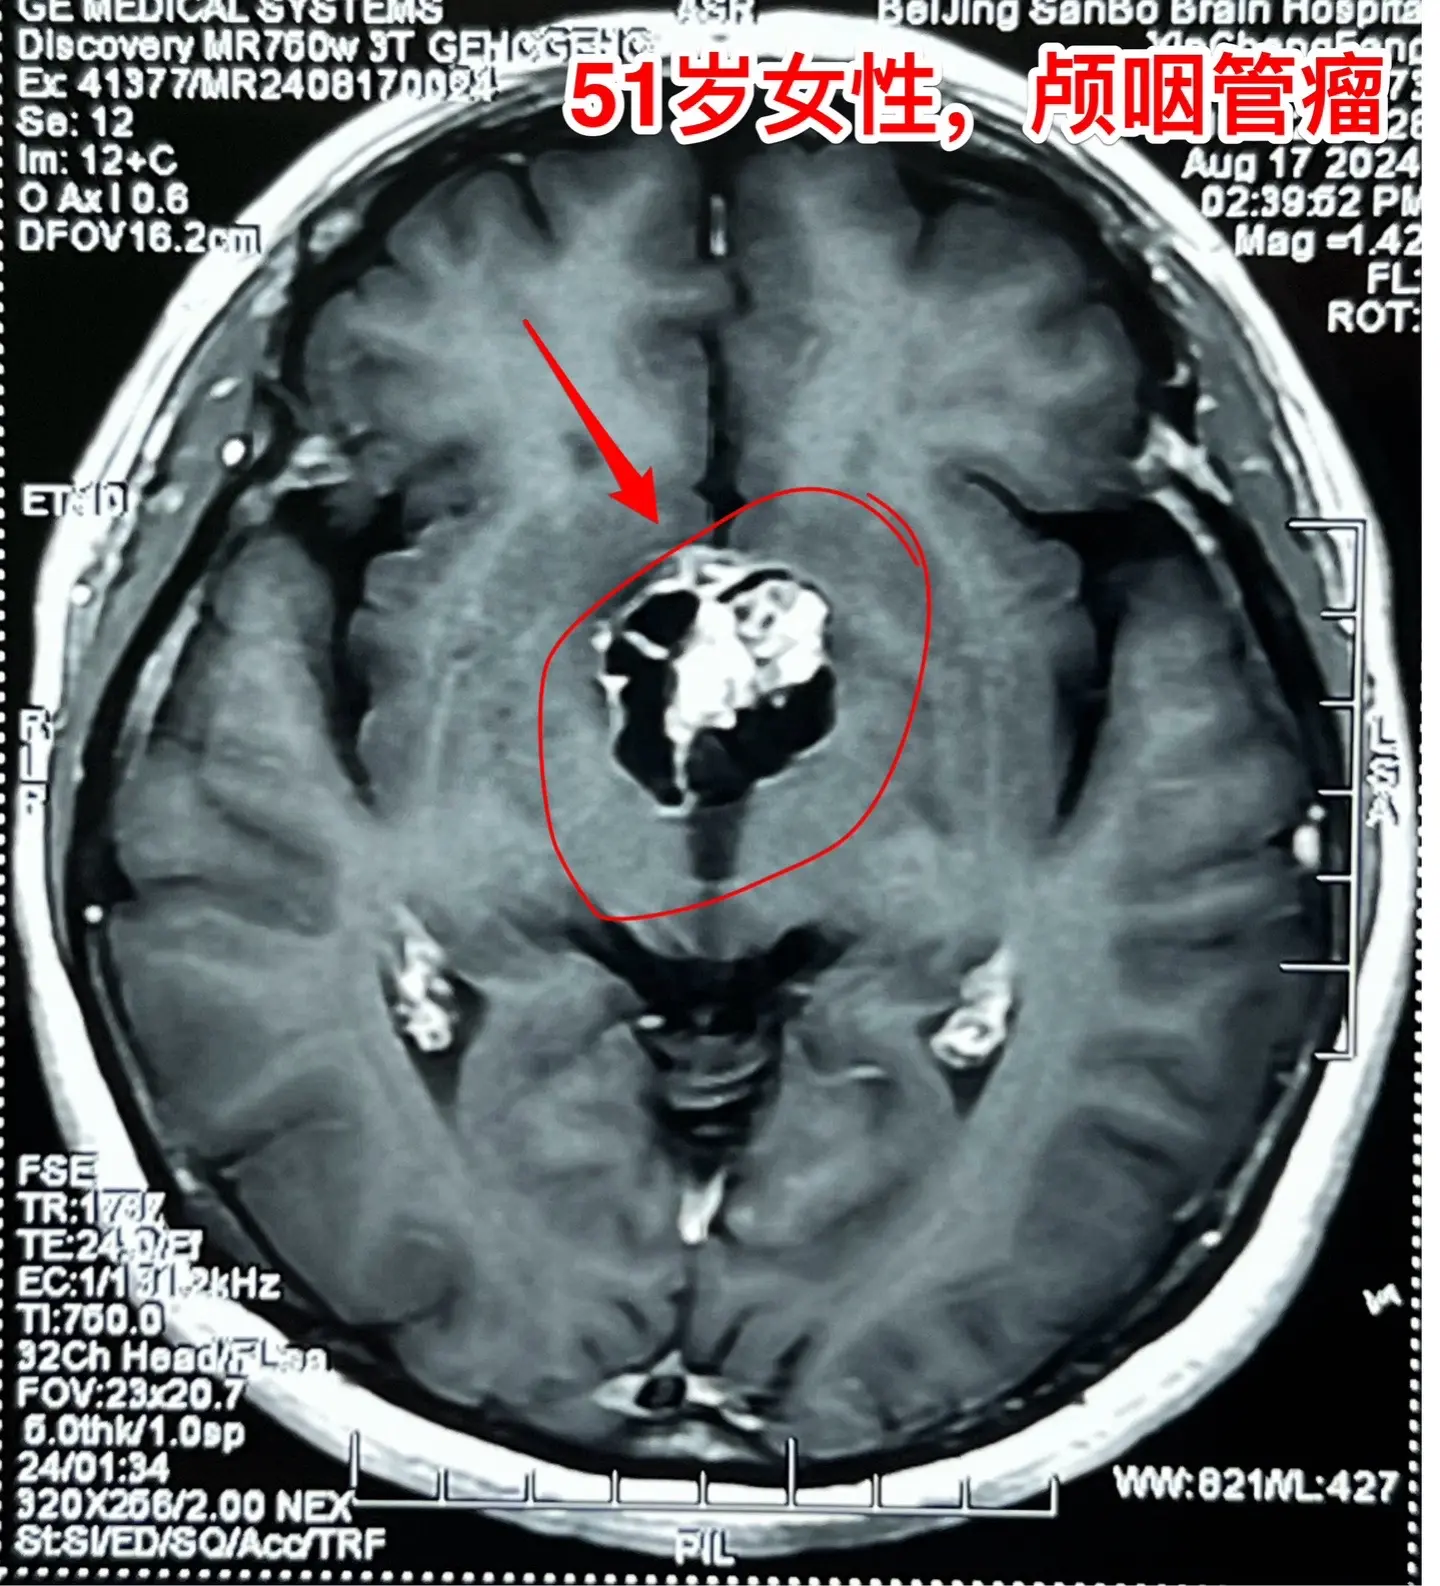

视频中展示出来的是第一个和第三个病人的影像学资料。

第一个病人女性,51岁,山东人。患者的弟弟就是神经外科医生。病人因为视力下降、困倦、无精打采到医院检查发现颅咽管瘤,是乳头型颅咽管瘤。患者家人一致要求作开颅手术切除颅咽管瘤。今天的手术很顺利,颅咽管瘤得到完全切除,晚上病人作完了CT就从ICU转到普通病房了。